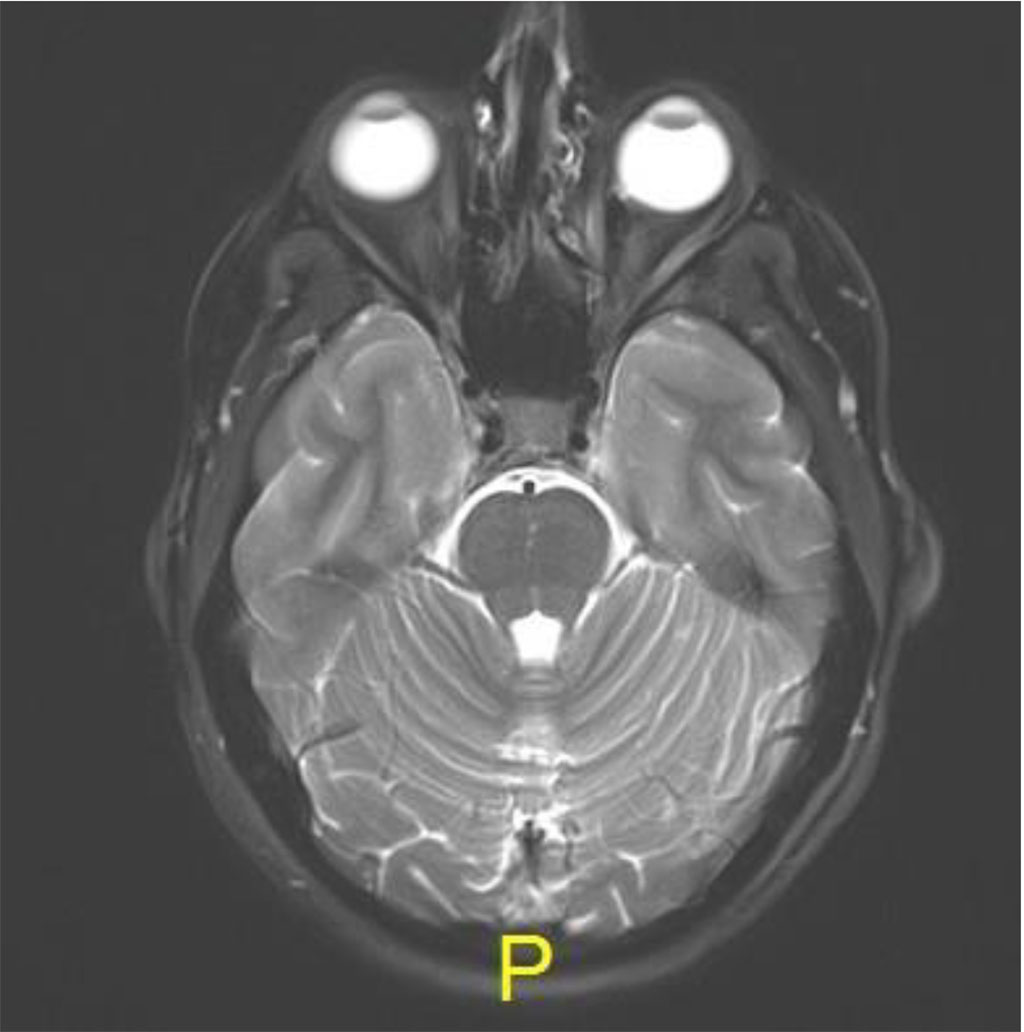

Following the procedure, the patient complained of diplopia in primary position with restriction of upgaze. The patient was treated with oral steroids with no improvement. MRI was 2 months post procedure, there was excellent anatomical improvement, with significant decrease of the lesion but with enlargement of the inferior rectus (Figures 4 a,b,c).

Figure 4a: Axial MR T2: resolution of lesion